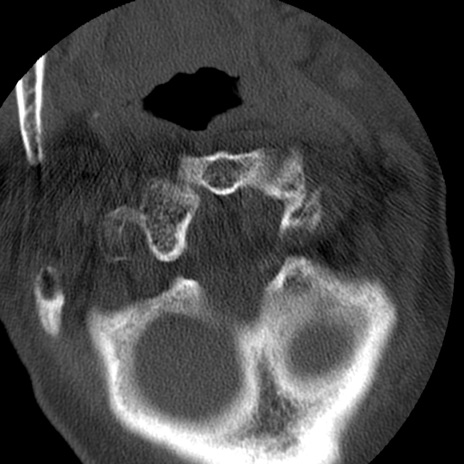

症例50 頚椎CT(横断像)

矢状断像